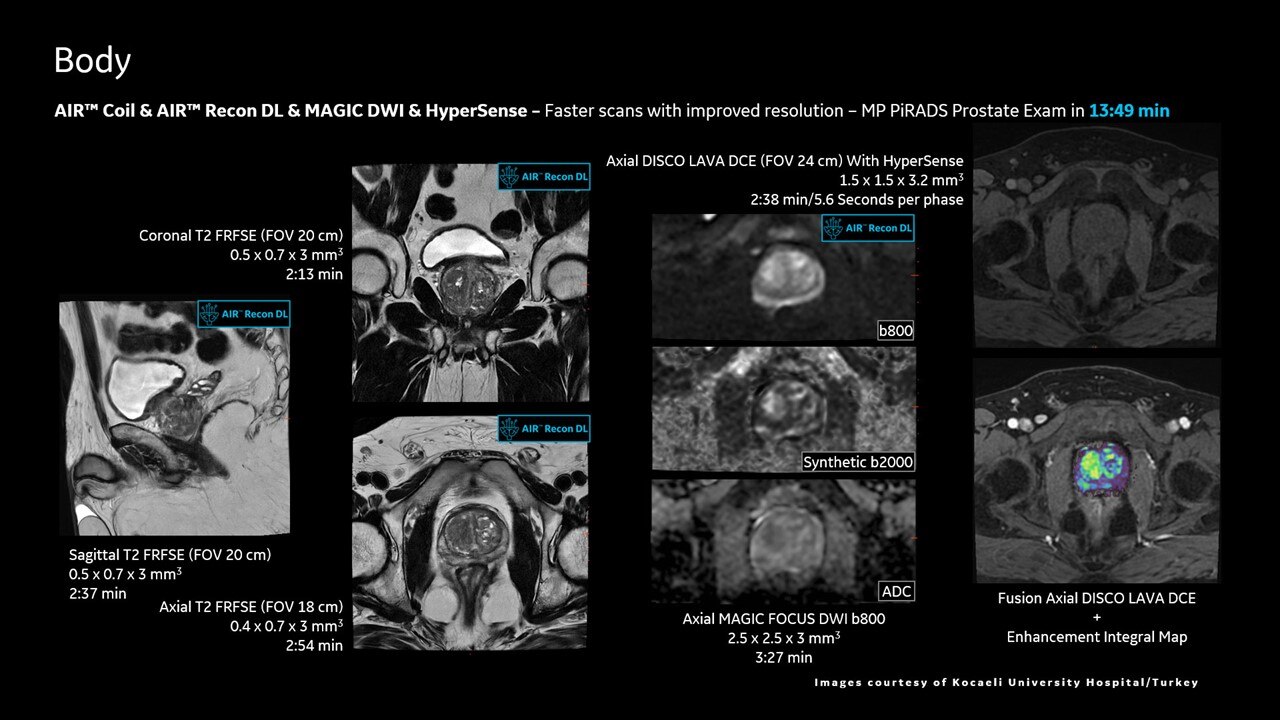

AIR™ Recon DL improves SNR and image sharpness, enabling shorter scan times

Achieve a 25% efficiency gain with Ultra High Efficiency (UHE) gradient system. Fast, clear Total Digital Imaging (TDI) increases SNR by 25%. Improved IQ in 80% of cases without added time. Acquire higher SNR without a time penalty and get images virtually free of artifact with AIR™ Recon DL.***